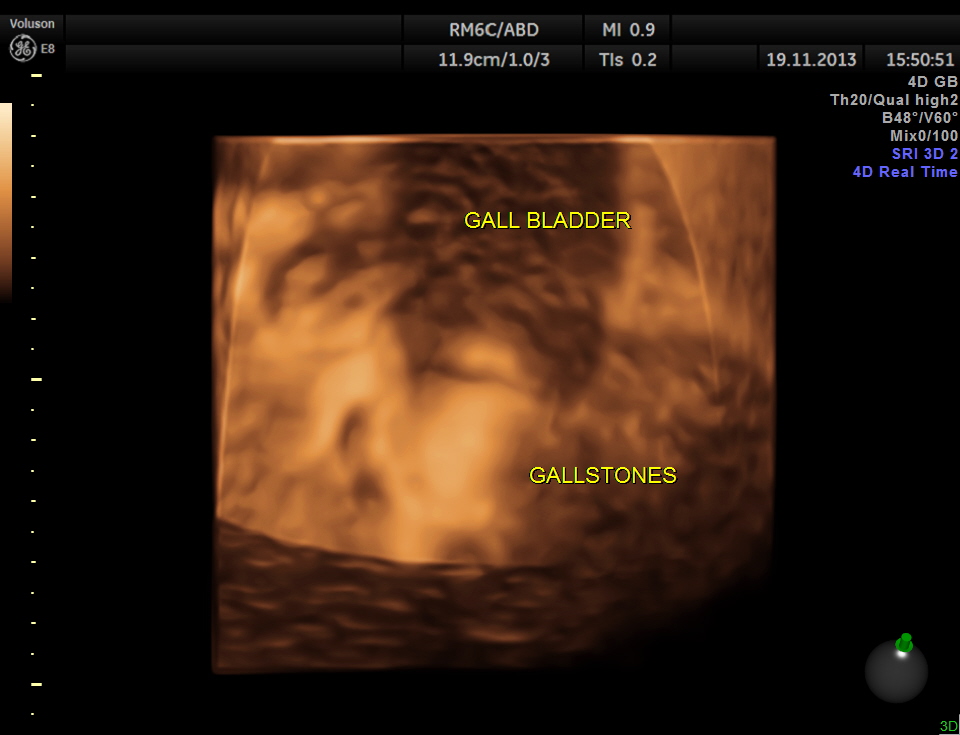

Her abdominal scan revealed a distended gall bladder with two big gallstones and one of them was obstructing the cystic duct.

She had acute cholecystitis with gallstones causing obstruction of the cystic duct.